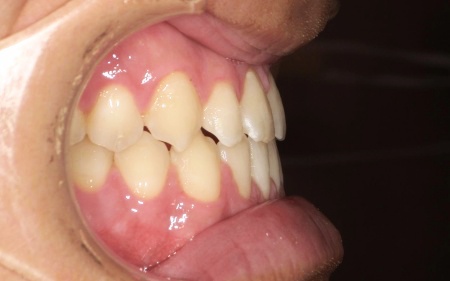

最後に、歯並びと噛み合わせが整い、見た目にも問題がないことを確認し、治療を終了しています。

矯正期間:30ヶ月

(通院間隔1~2ヶ月)

保定期間:24ヶ月

(通院間隔3~4ヶ月) - 治療回数の目安 -